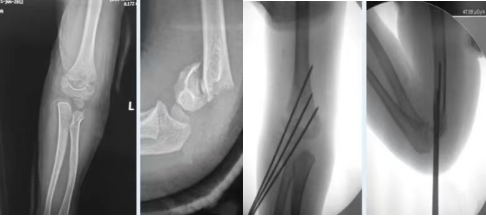

肱骨髁上骨折是发生在肱骨远端内外髁上方2cm以内的骨折。是儿童上肢骨折中最常见的一种类型,约占儿童肘部骨折的50%~60%,好发年龄为4~10岁,可合并血管神经损伤,若不及时正确处理,晚期可发生缺血性肌挛缩、肘内翻等并发症。

(1)闭合复位后经皮穿针固定:儿童患者大多采用此方法。是一种微创、安全、有效、骨折愈合快、并发症少的优点。